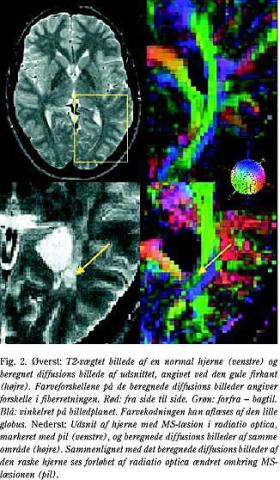

I den normale hjerne er diffusionen af vandmolekyler begrænset af cellulære strukturer som myelin, makromolekyler og celleorganeller. Derfor er den diffunderede afstand kortere og den målte diffusionskoefficient ADC (apparent diffusion coefficient) lavere end ved fri diffusion i vand (19). Patologiske processer, der ændrer vævets opbygning, som fx demyelinisering, kan øge ADC ved at fjerne nogle af diffusionsbarriererne. I CNS er vanddiffusion næsten upåvirket parallelt med nervefibre, mens den er begrænset på tværs af fiberretningen (19, 20) (anisotrop diffusion). Diffusionsvægtet MR kan således fortælle om fiberretningen samt give oplysninger om størrelse og geometri af forskellige hjernestrukturer og patologiske forandringer (21) (Fig. 2).

Hos MS-patienter har man fundet højere ADC-værdier og dermed øget diffusion i både læsioner og tilsyneladende normal hvid substans (20, 22, 23). Man mener, at dette skyldes et øget ekstracellulært volumen forårsaget af ødem, demyelinisering eller axontab. Samtidig mindskes anisotropien. Det vil sige, at diffusionen bliver mere ensartet i rummet, hvilket skyldes tab af fiberorienteringen på grund af demyeliniseringen (24).